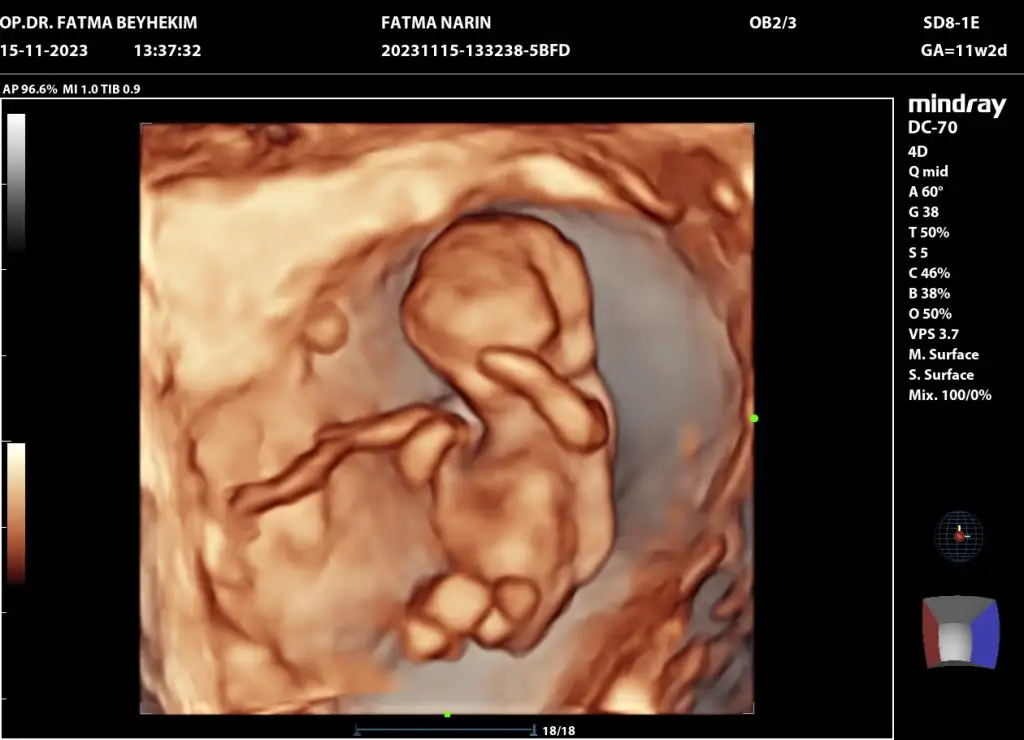

Kızlar bugün kontrolüm vardı şuan 12.haftamın içindeyim 2 li tarama yapıldı ama cinsiyetine erken olduğu için doktor bir şey demedi. Bir ay sonraya çağırdı gerçekten merak ediyorum tecrübeli olanlar varsa tahmin edebilir miBi de 2 gün geç döllenme olmuştu başta ama şuan 1 gün önden gidiyormuş belki işinize bana da yorum yaparmisiniz bende çok merak ediyorum

Bana da yorum yaparmisiniz bende çok merak ediyorumKızlar bugün kontrolüm vardı şuan 12.haftamın içindeyim 2 li tarama yapıldı ama cinsiyetine erken olduğu için doktor bir şey demedi. Bir ay sonraya çağırdı gerçekten merak ediyorum tecrübeli olanlar varsa tahmin edebilir miBi de 2 gün geç döllenme olmuştu başta ama şuan 1 gün önden gidiyormuş belki işinize yarar